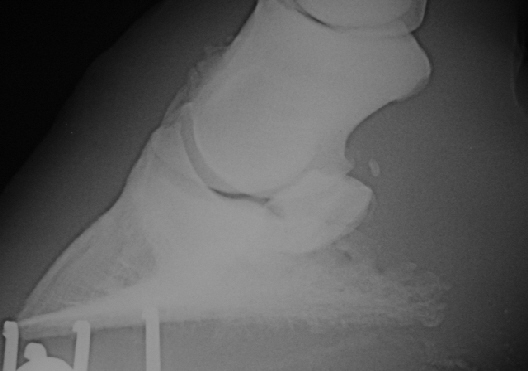

Bei diesem Pferd ist die Zehenachse gebrochen, die Trachten sind flach, das Hufbein ist in der Hornkapsel abgesunken bei leicht negativem Hufbein-Bodenwinkel, die Pfeile zeigen den veränderten Insertionsbereich von unterem Strahlbeinband und tiefer Beugesehne an. Der Stoßdämpfer dieses Pferdes ist  zerstört.